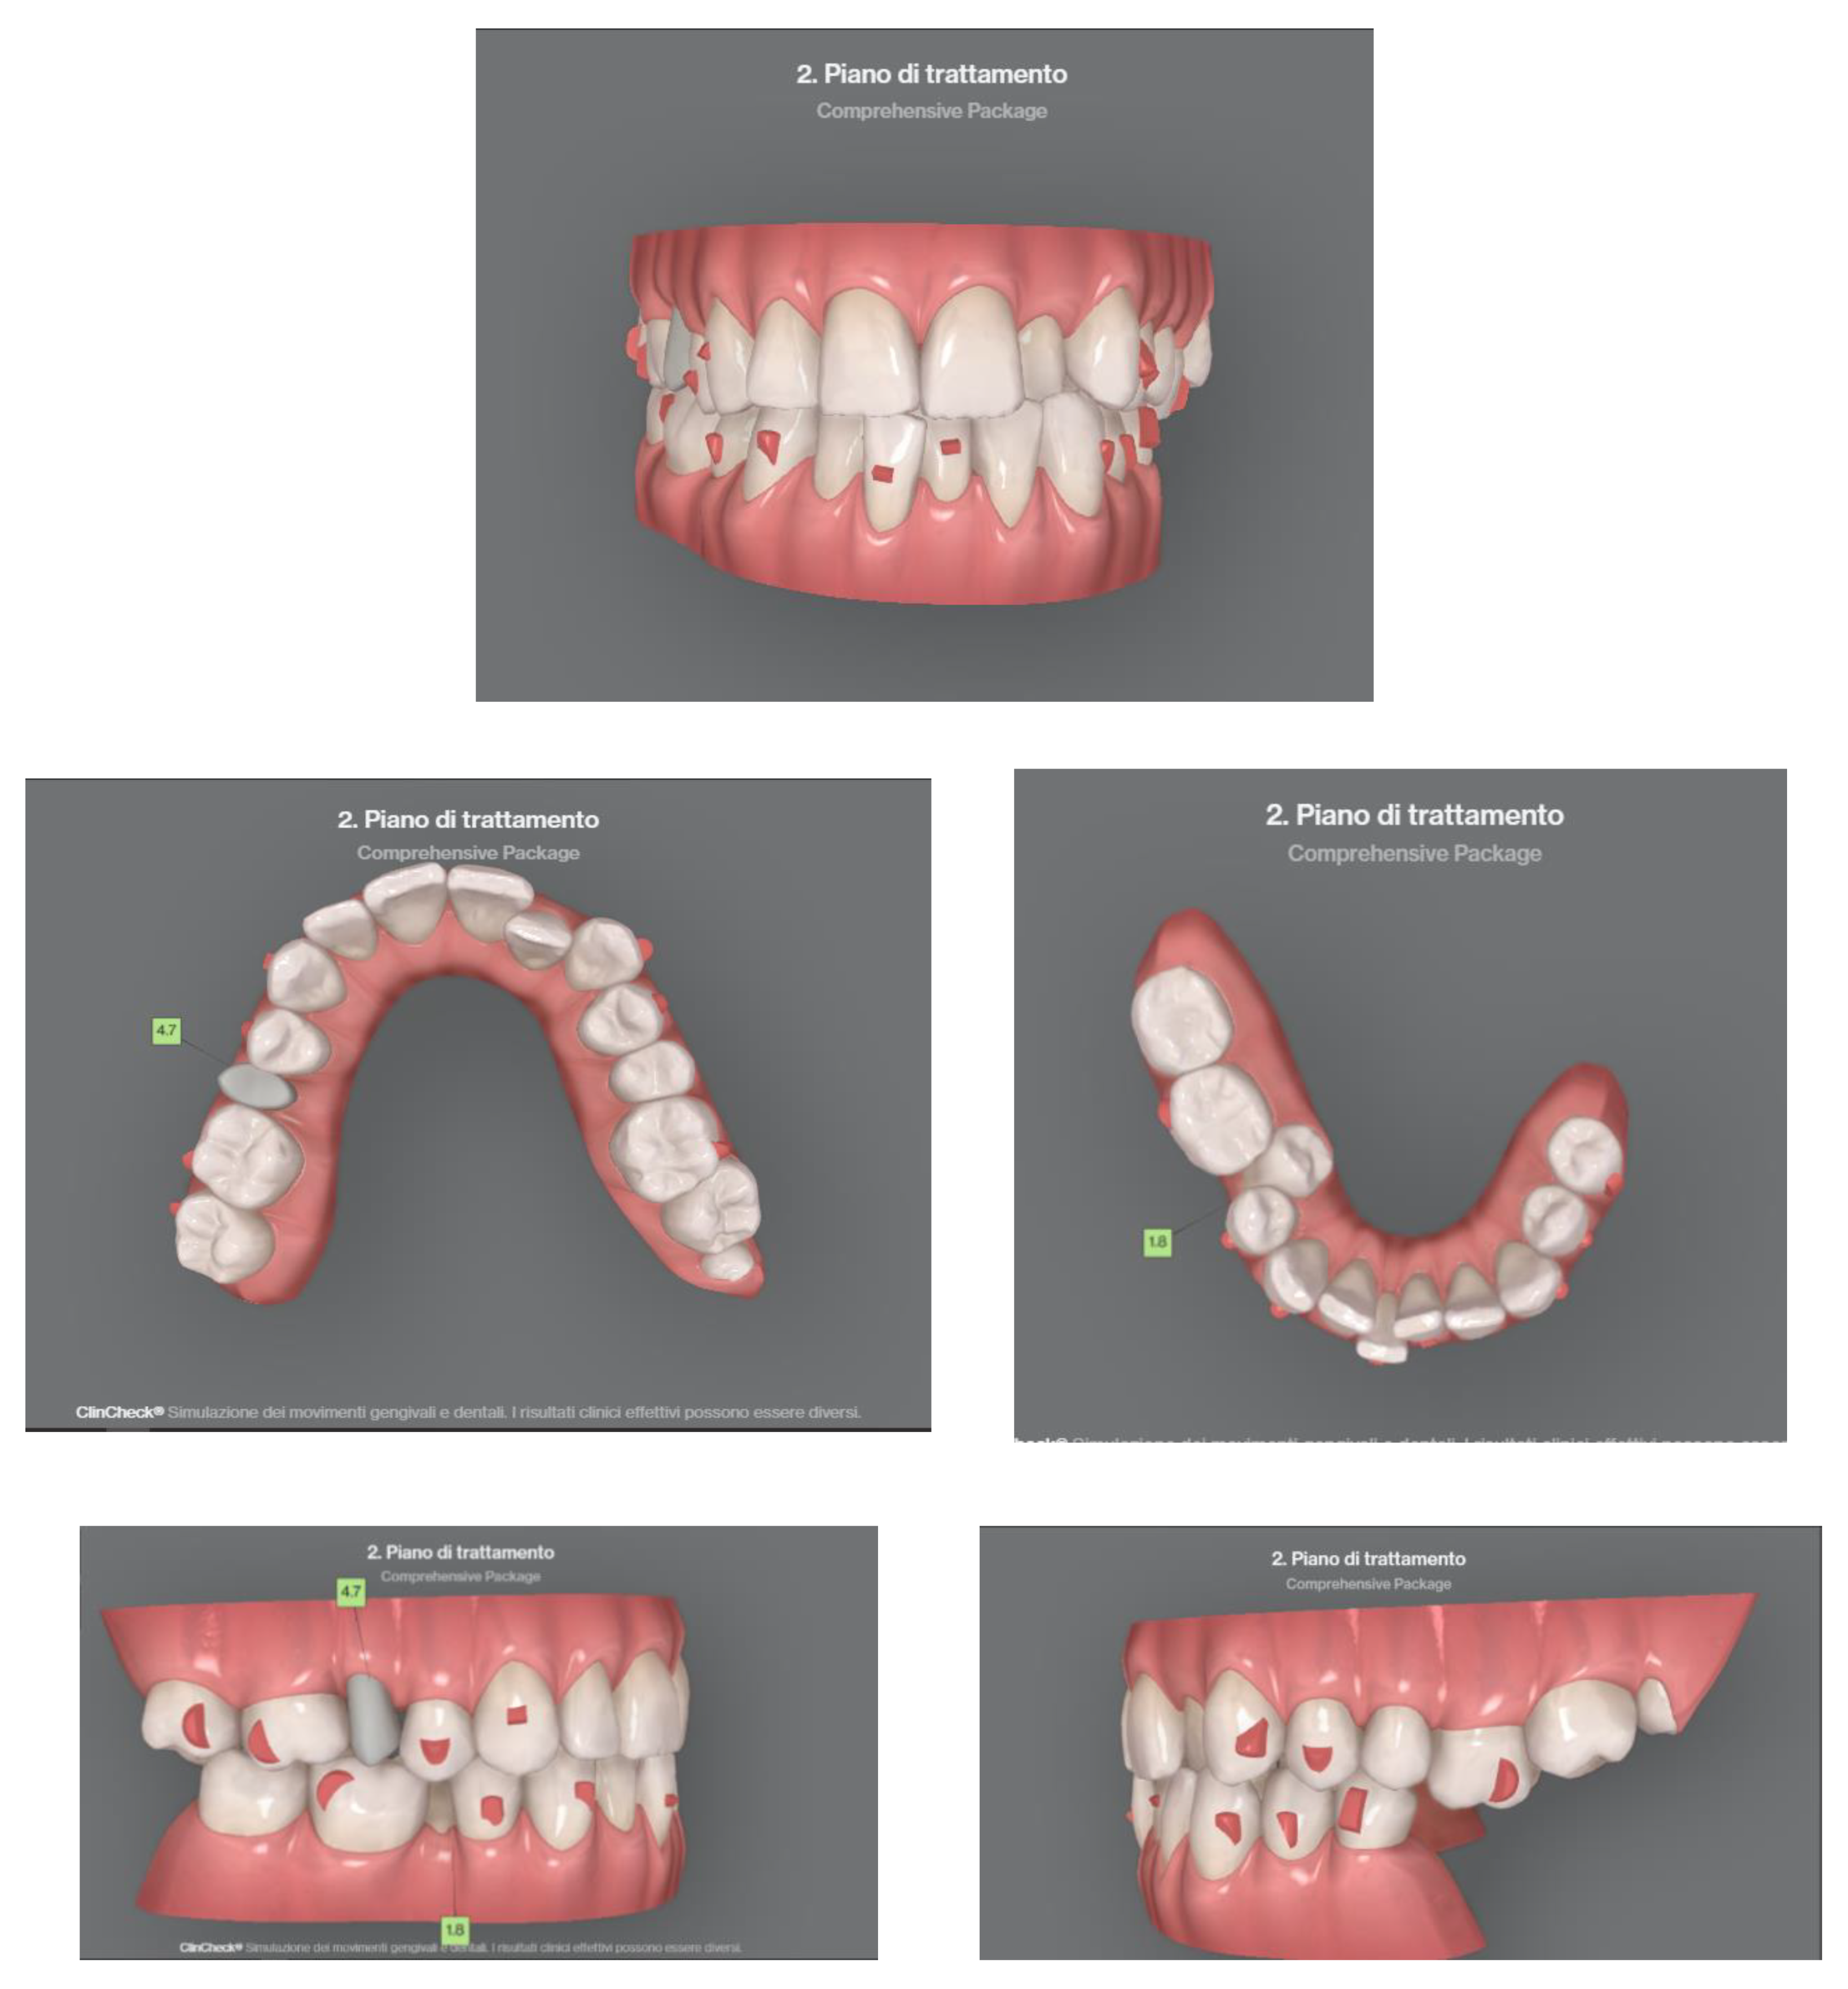

Case 2 concerns a 57-year-old male, with no systemic diseases. He came to our observation in November 2019, to carry out an orthodontic treatment to improve the esthetic appearance of his smile. He showed a good oral hygiene and periodontal condition. Intra-oral evaluation showed a reduction of the transverse diameters, both in the upper and lower dental arches, and a lack of space for the tooth 4.5 in the lower arch (Figure 9 and Figure 10). It was planned to re-establish elements 1.6 and 3.6 after orthodontic therapy in order to reach the first molar class. The most important problem for the patient was related to his smile esthetics and concerned the crossbite of the tooth 2.2.

Figure 10. Clinical case treated with Invisalign© aligners. Intraoral views from ClinCheck. Frontal, upper, and lower occlusal and lateral view of occlusion before the beginning of treatment.